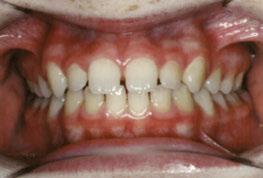

Figures 1A and 1B: Adolescent with anterior open bite: Orthognathic surgery unnecessary post-myofunctional therapy. 1A. Pre-myofunctional therapy: The bite only touched on the back molars, yet the patient had already gone through full braces. The original orthodontist recommended orthognathic surgery to close the bite. The patient was referred for a second opinion. The second orthodontist recognized the tongue thrust and referred the patient for myofunctional therapy but made no guarantees that the patient would not need jaw surgery. 1B. Post-myofunctional therapy: After 2.5 years of braces and myofunctional therapy, the orthodontist gave the patient the good news that jaw surgery would not be necessary. The myofunctional therapy allowed the orthodontist to close the bite once the tongue pressure was removed from between the teeth

Figures 2A and 2B: Open bite corrected with myofunctional therapy. 2A. Pre-myofunctional therapy: This patient was in braces for 3 years with no success at closing the open bite. 2B. Post-myofunctional therapy: After 5 months of myofunctional therapy to address the mouth breathing and tongue thrust, the open bite closed

Figures 3A and 3B: 3A. Pre-myofunctional therapy: Anterior open bite caused of soft tissue dysfunction including incorrect lingual rest posture and tongue thrust. 3B. Post-myofunctional therapy: 4 years after the start of myofunctional therapy with no orthodontic treatment, and the open bite closed. By taking the tongue pressure off of the teeth in OMT, the occlusion was able to normalize. The orthodontist feels the patient does not need braces

Figures 4A and 4B: Unilateral open bite developed later in life. 4A. This patient’s unilateral open bite was due to a change in muscle function, as after a left root canal, the patient began to only chew on the right side. This chewing pattern changed the muscle balance as the patient continually spread the right side of the tongue to push food onto the teeth. There was no orthodontic progress, and the patient was referred for orofacial myofunctional therapy. 4B. OMT restored muscle development, resting tongue posture, correct chewing function, and correct swallowing. In 5 months, the patient was debanded